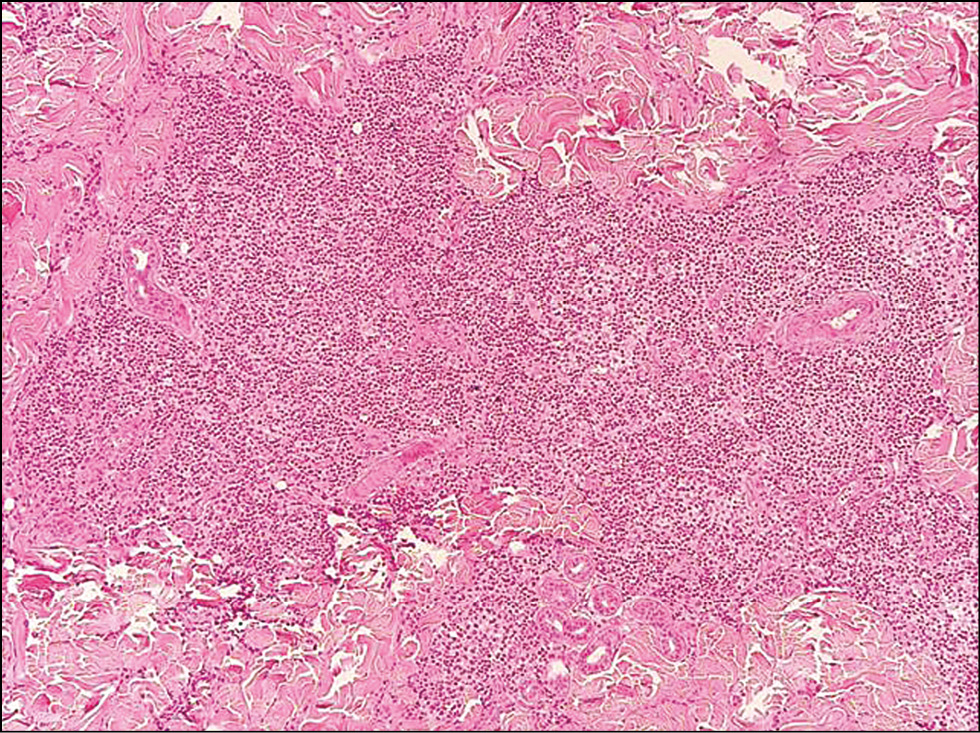

Изучение патоморфологических особенностей ДЛК позволило выделить её основные черты. Лимфоцитарный инфильтрат, состоящий преимущественно из малых В-лимфоцитов, плазматических клеток, гистиоцитов, макрофагов, нейтрофильных и эозинофильных форм гранулоцитов, в большинстве случаев располагался в верхних (n=16; 53%) и средних (n=11; 36,7%) слоях дермы, однако при ДЛК, представленной узлами (n=3; 10%), он распространялся и на подкожно-жировую клетчатку (рис. 6). Во всех случаях наблюдалась сохранность придатков кожи с перифокальными инфильтратами, а также пролиферация микрососудов (рис. 7). Из 30 больных ДЛК у 8 (26,7%) в коже были обнаружены фолликулоподобные структуры (рис. 8), у 6 (20%) ― лимфоидные фолликулы с герминативными центрами (рис. 9). Лимфоидные фолликулы различных размеров имели характерные чёткие границы с широким ободком из мелких лимфоцитов. В герминативном центре лимфоидных фолликулов наблюдались многочисленные митозы. При иммуногистохимическом исследовании кожи в биоптатах всех больных ДЛК в дермальном инфильтрате было выявлено преобладание CD20+ В-лимфоцитов (рис. 10) Соотношение IgL κ/λ составило примерно 1:1 во всех биоптатах (рис. 11, 12). По результатам ПЦР-анализа: по реаранжировкам генов IgH B-клеточная клональность не выявлялась в большинстве случаев (n=25; 83%), в 5 (17%) ― результат был интерпретирован как сомнительный.

Рис. 10. Иммуногистохимическое исследование кожи: CD20+ В-лимфоциты в лимфоидных фолликулах, ×200. / Fig. 10. Immunohistochemical examination of the skin: CD20+ B-lymphocytes in lymphoid follicles, ×200.